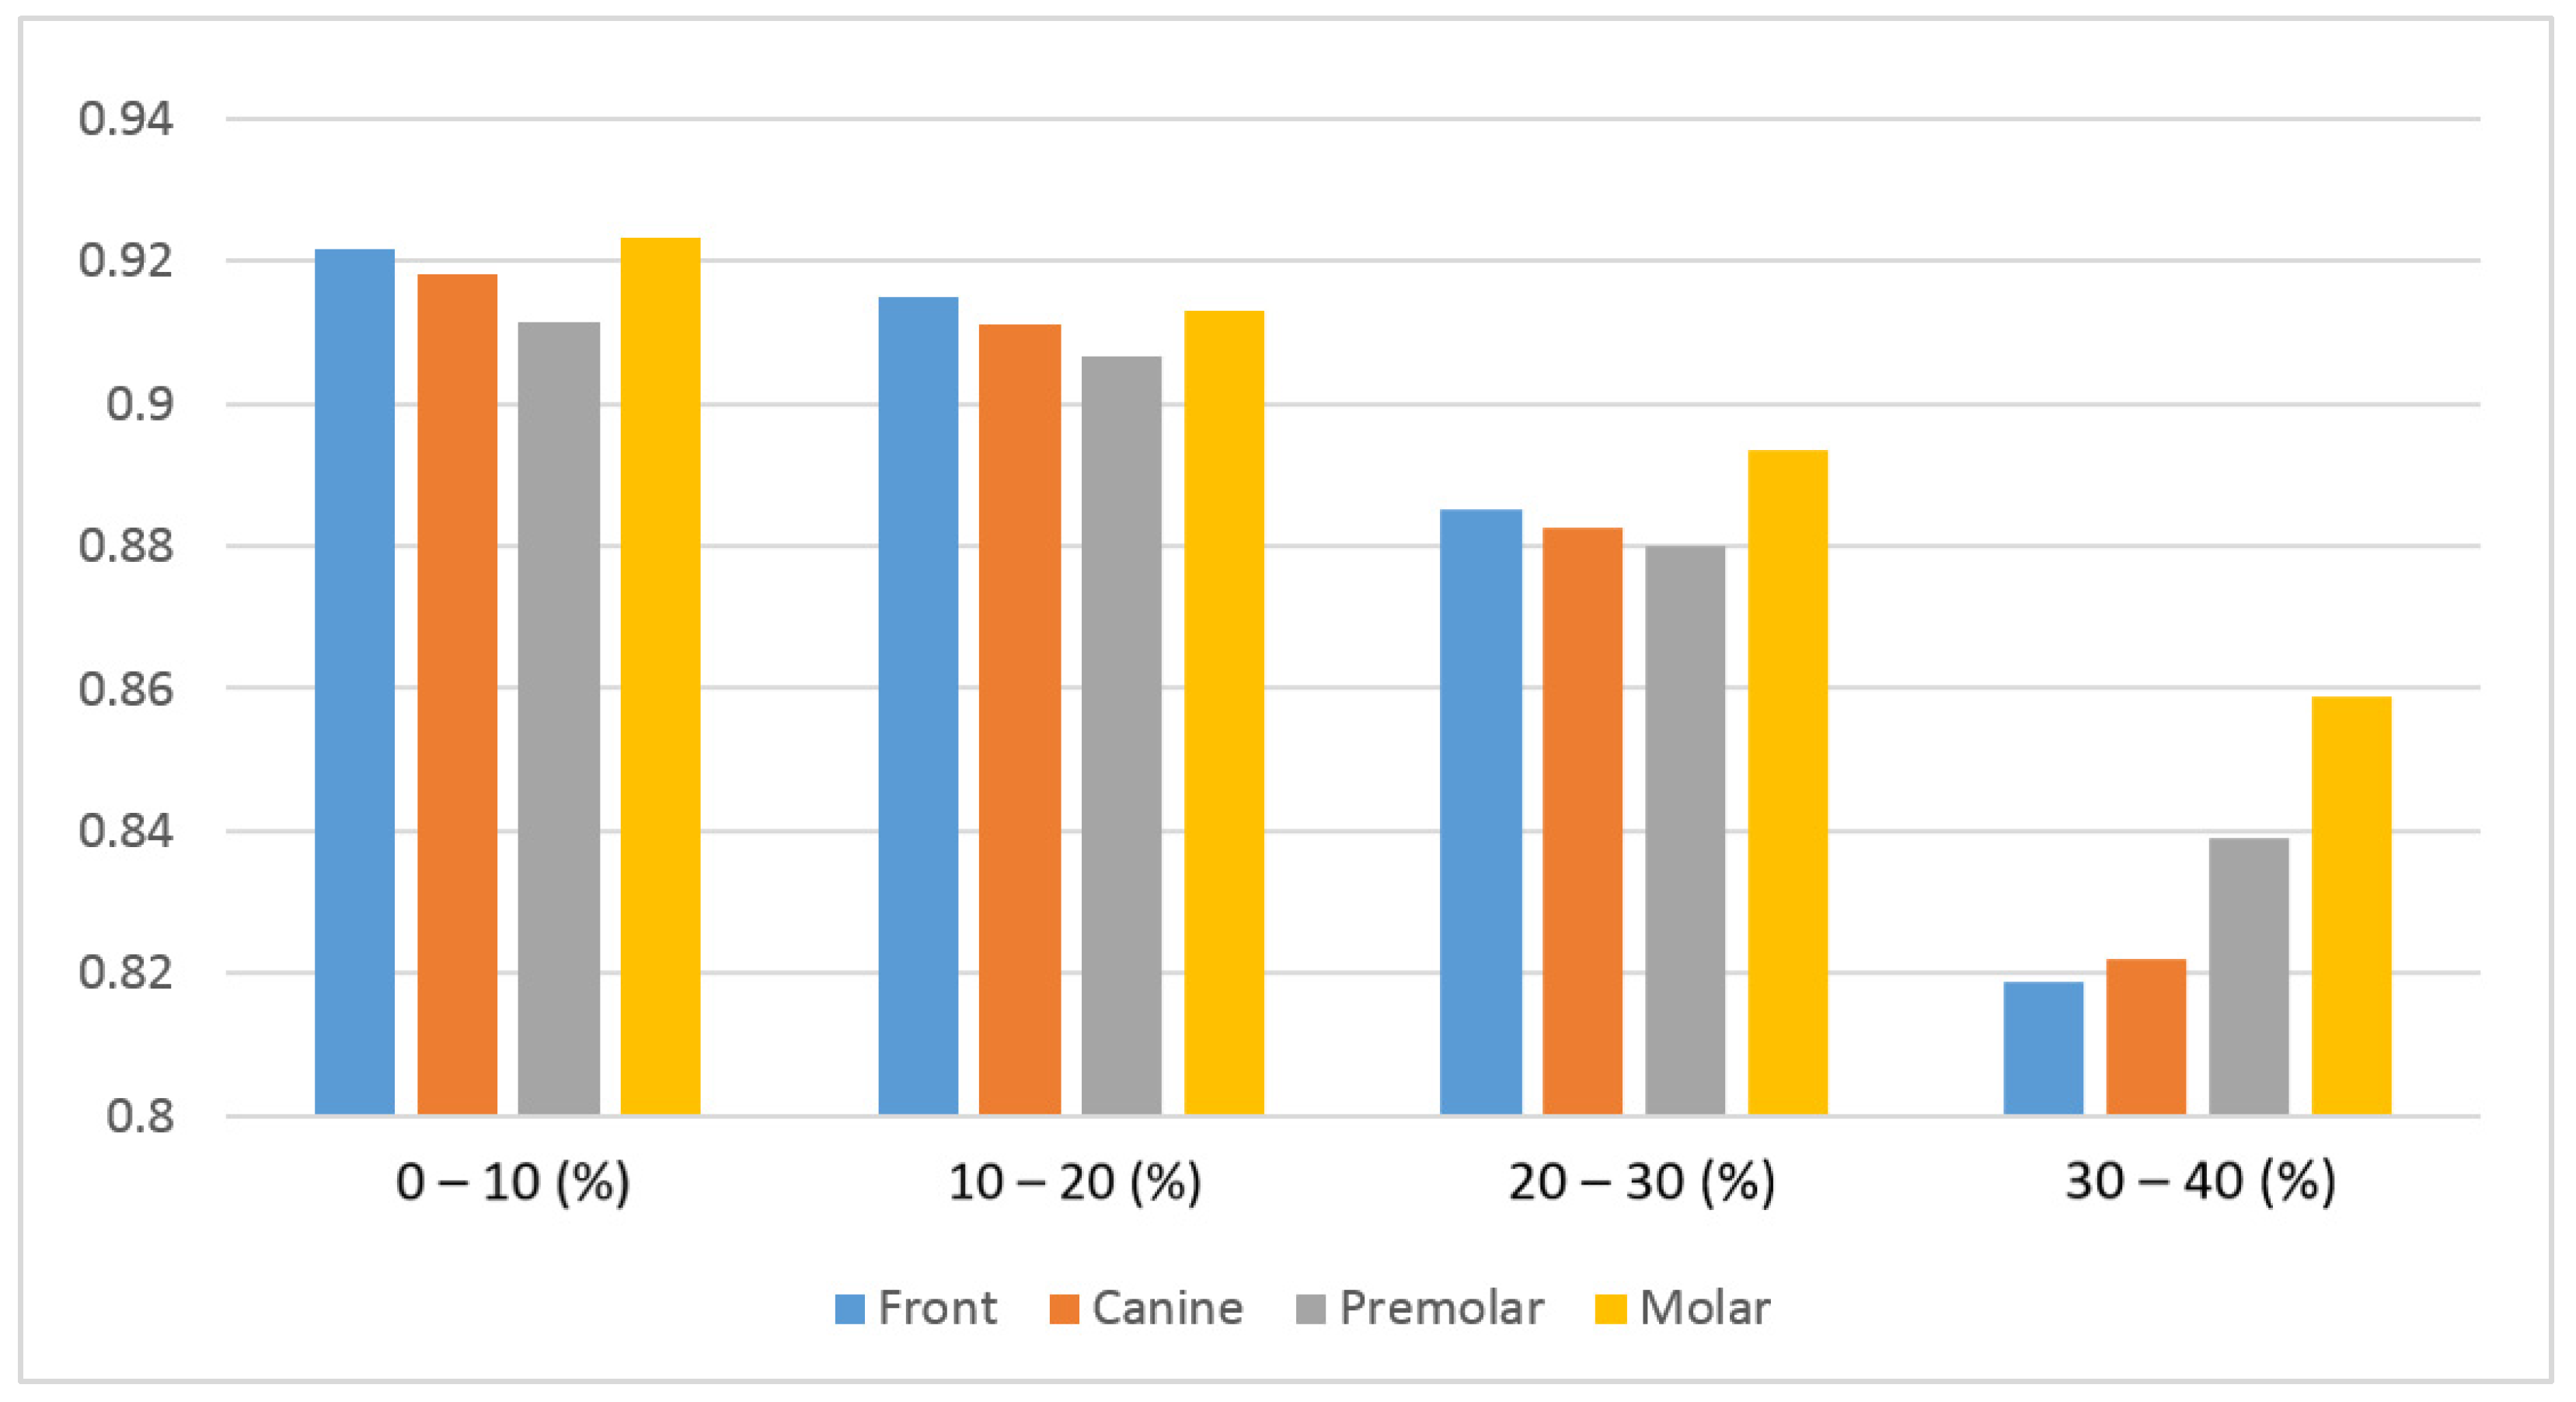

3.2.3. Measurement Accuracy Results

| Mask | Incisor | Canine | Premolar | Molar |

|---|---|---|---|---|

| 0–10% | 0.921 | 0.918 | 0.911 | 0.923 |

| 10–20% | 0.915 | 0.911 | 0.906 | 0.913 |

| 20–30% | 0.885 | 0.883 | 0.879 | 0.894 |

| 30–40% | 0.819 | 0.822 | 0.839 | 0.859 |